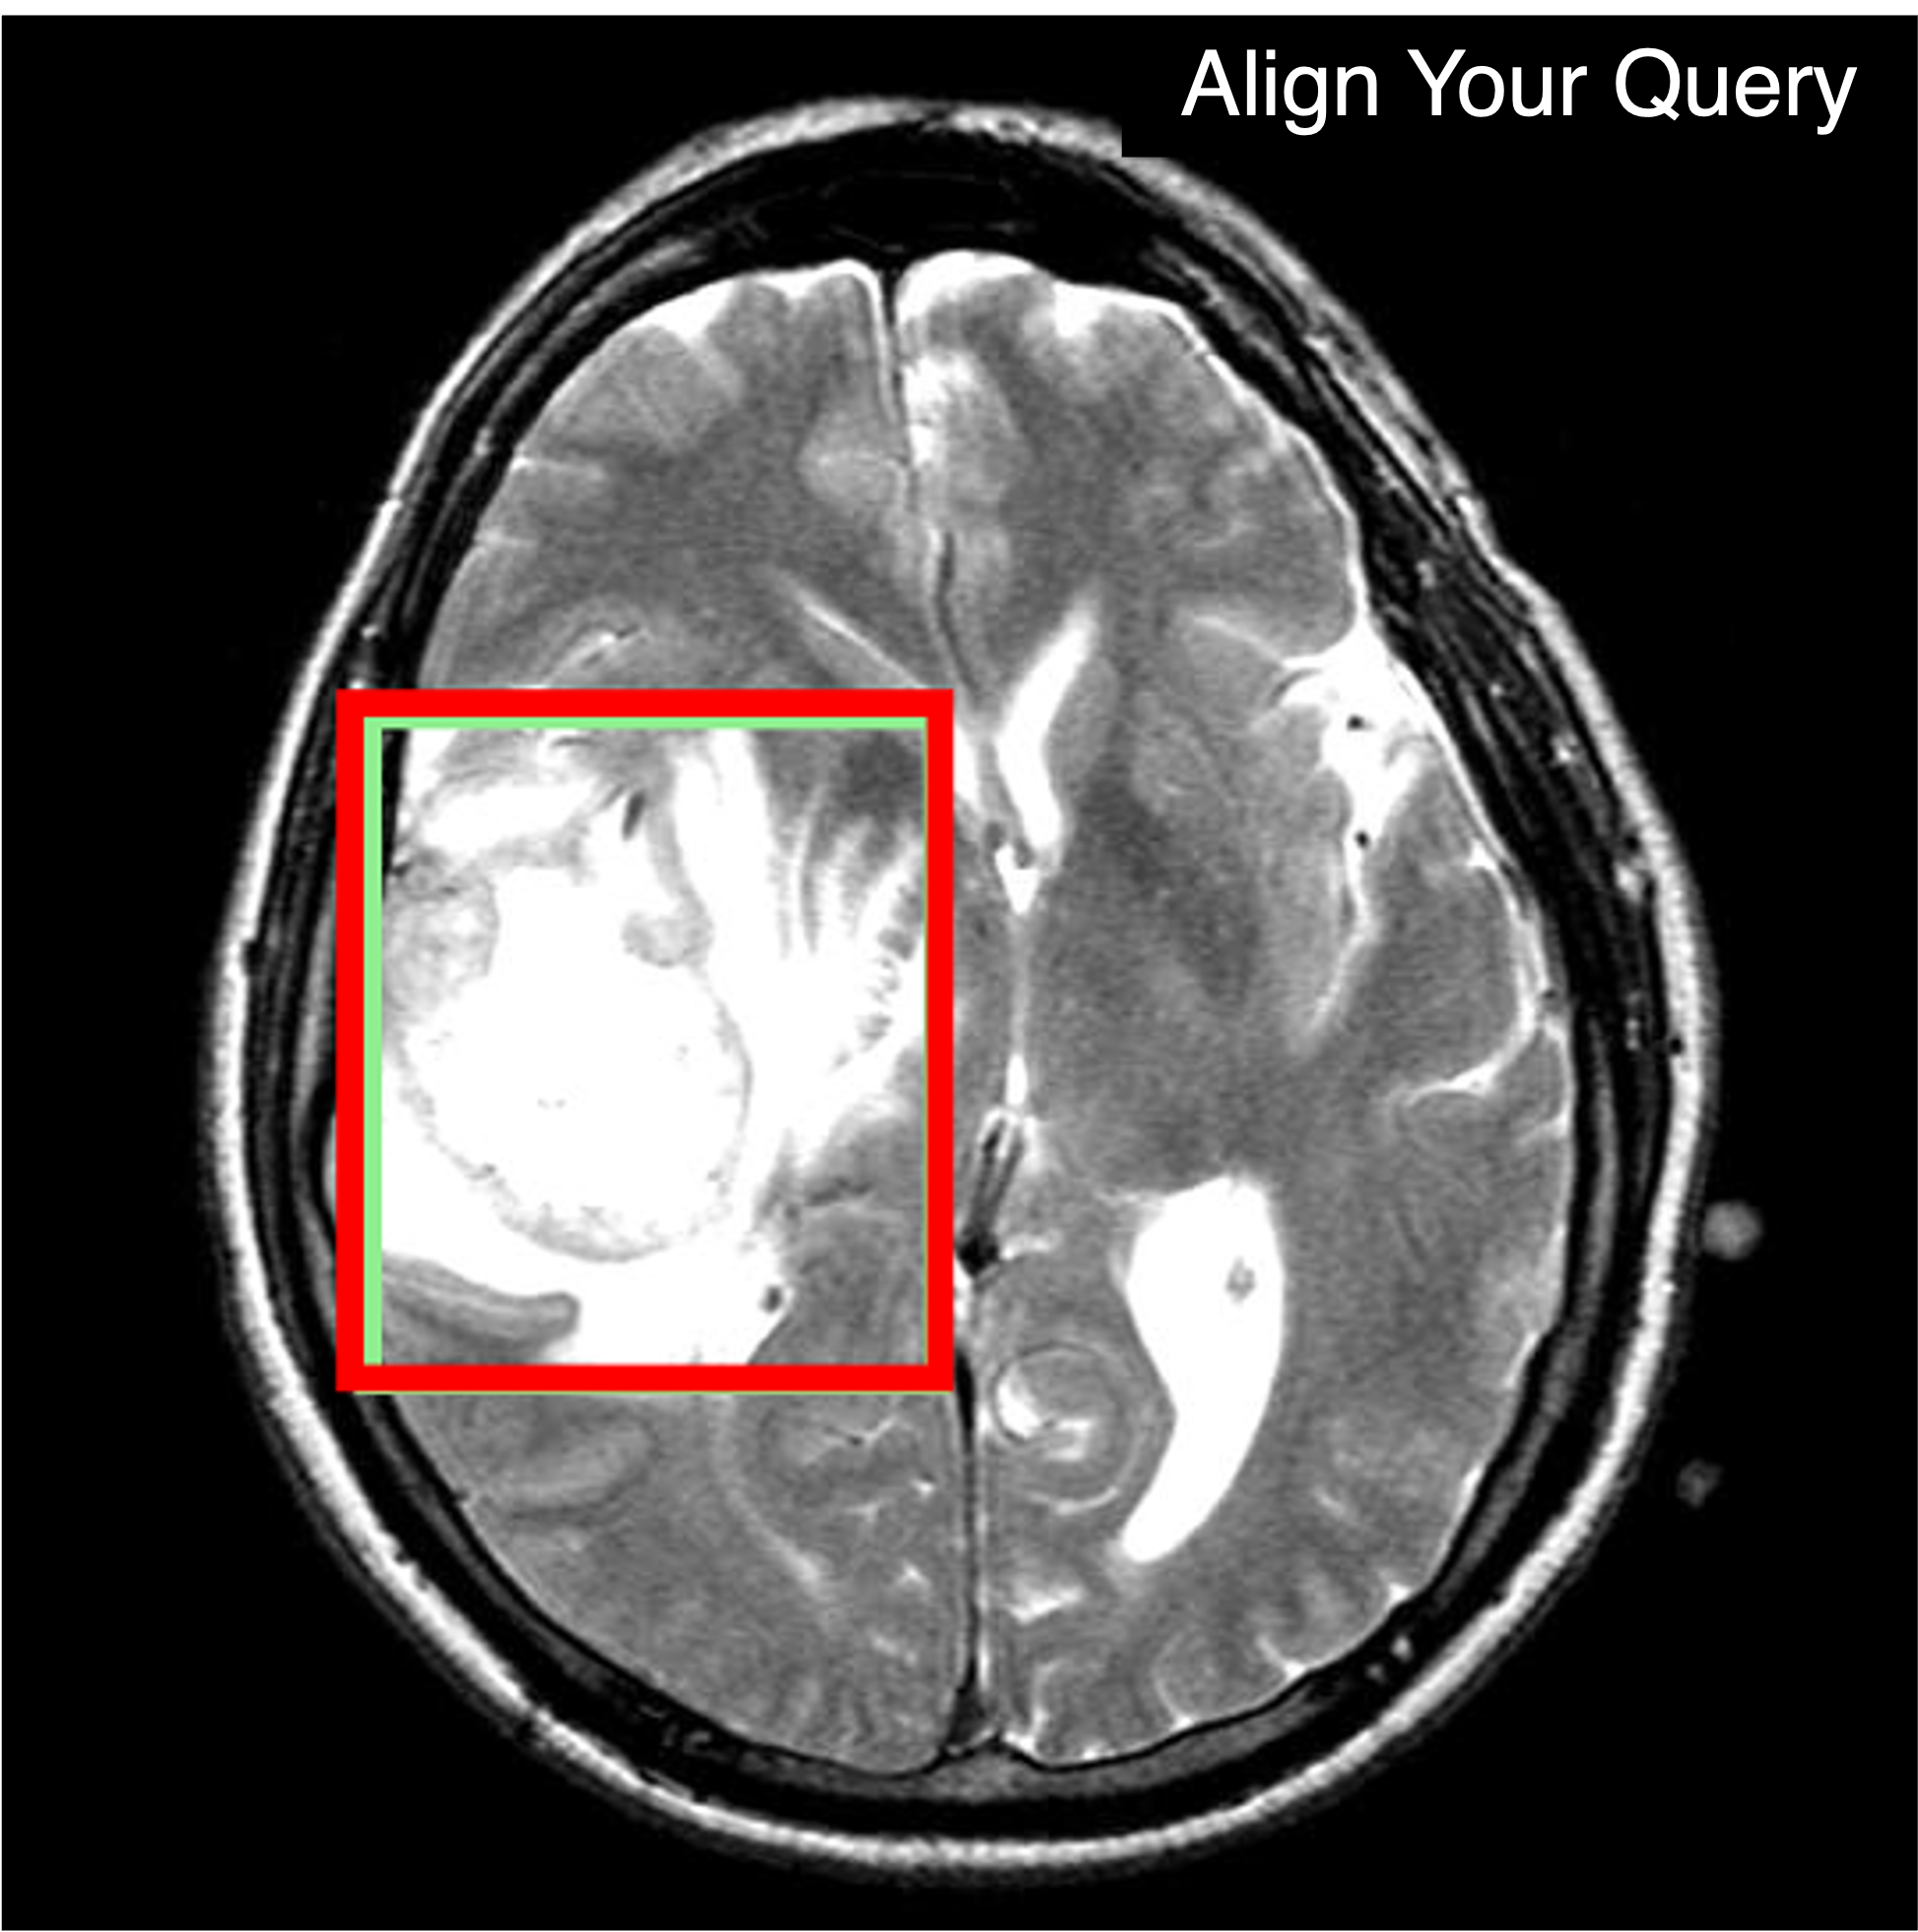

Qualitative comparison results

Qualitative Comparison. Comparison results between various state-of-the-art detection methods and the proposed method is shown above. Our method effectively leverages modality context to significantly enhance anomaly localization (red), compared to baseline results (blue). Ground truth bounding boxes are green. For cases where the bounding boxes are small, insets show an enlarged view of the highlighted yellow region.